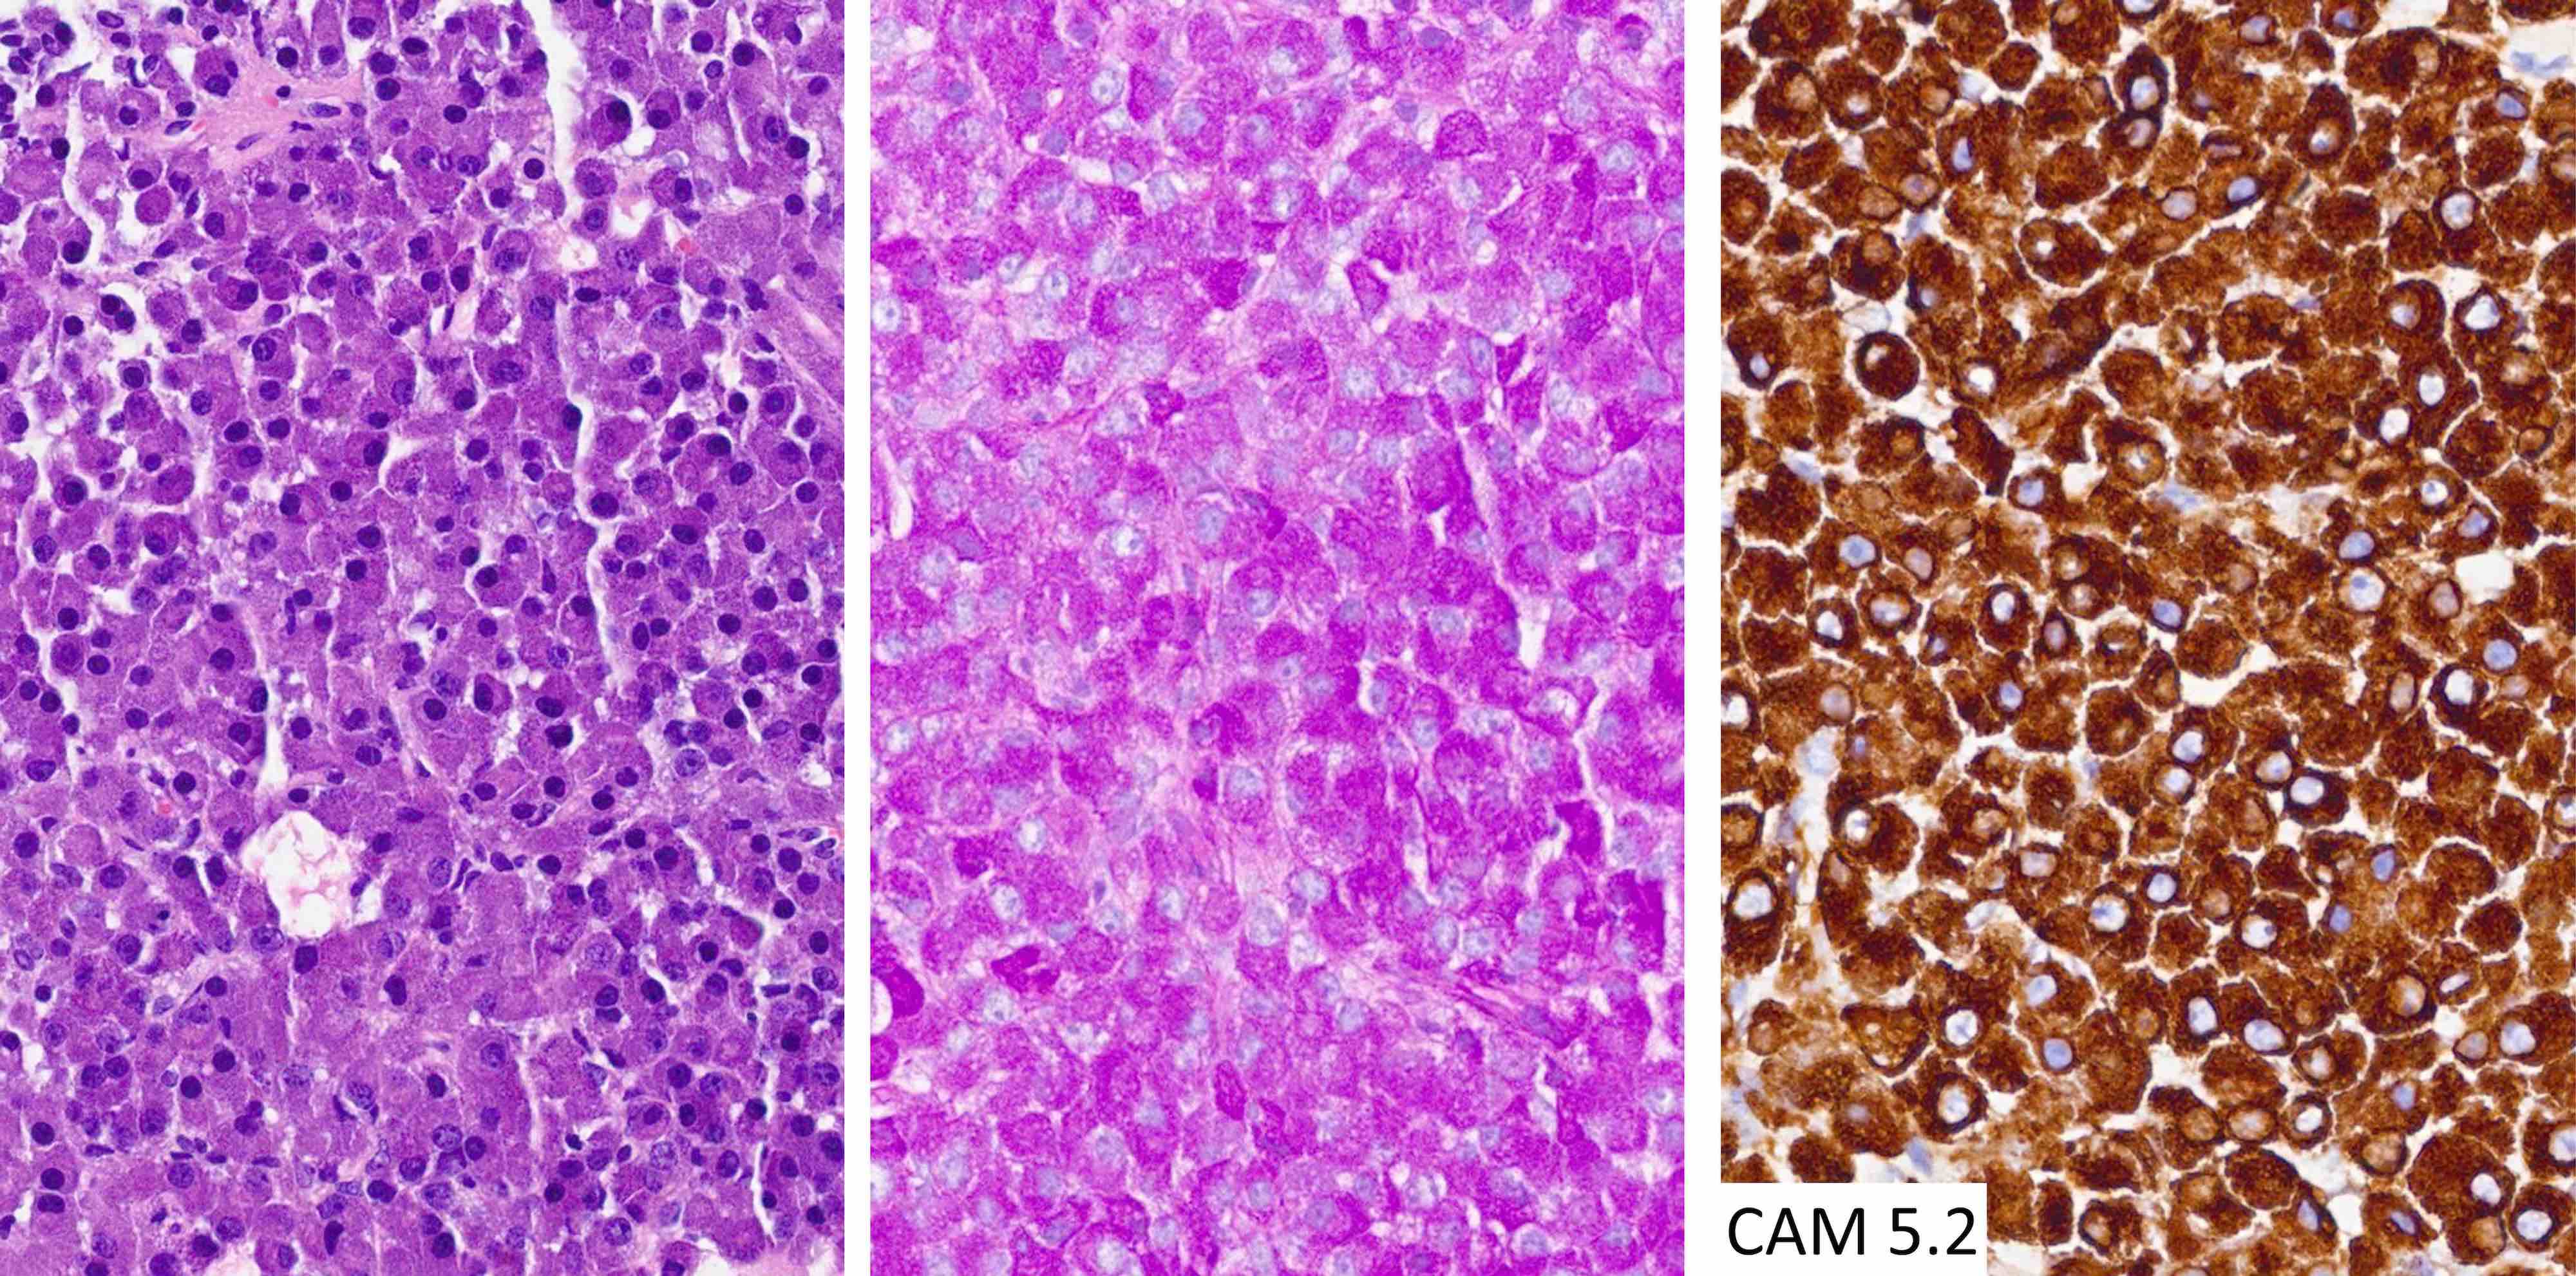

Microscopic (histologic) images

Contributed by Sylvia L. Asa, M.D., Ph.D.

Positive stains

- Diffuse and strong cytoplasmic CAM 5.2 staining is characteristic of corticotroph tumors